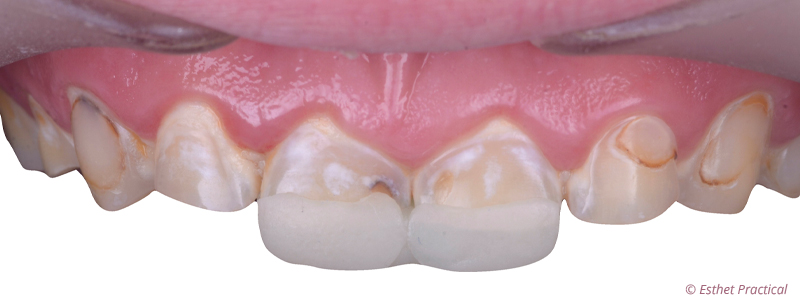

Fig. 02 : butée de surélévation à plan incliné oblique.

Une butée de surélévation à plan incliné oblique (composite bleu) est réalisée en palatin des 2 incisives centrales selon le concept du Jig de Lucia. Le but est de supprimer le guidage dentaire, de créer un recul mandibulaire, une fermeture dans l’axe charnière, de tester le volume à restaurer en palatin, de déterminer si un rallongement des incisives mandibulaires est aussi nécessaire et de contrôler la béance ainsi créée pour la restauration des 2 arcades. Cette simulation de l’augmentation de la dimension verticale permet enfin de vérifier son impact esthétique sur le visage.

On cherchera un point de contact unique centré entre les 2 incisives ou un point de contact équivalent sur la face palatine de chaque incisive centrale, validé par le marquage d’un papier d’occlusion fin.

Cette butée peut être complétée par un rallongement incisal (composite blanc) permettant de vérifier la longueur des bords incisifs par rapport à la courbure de la lèvre inférieure et de guider plus objectivement le design du futur sourire.